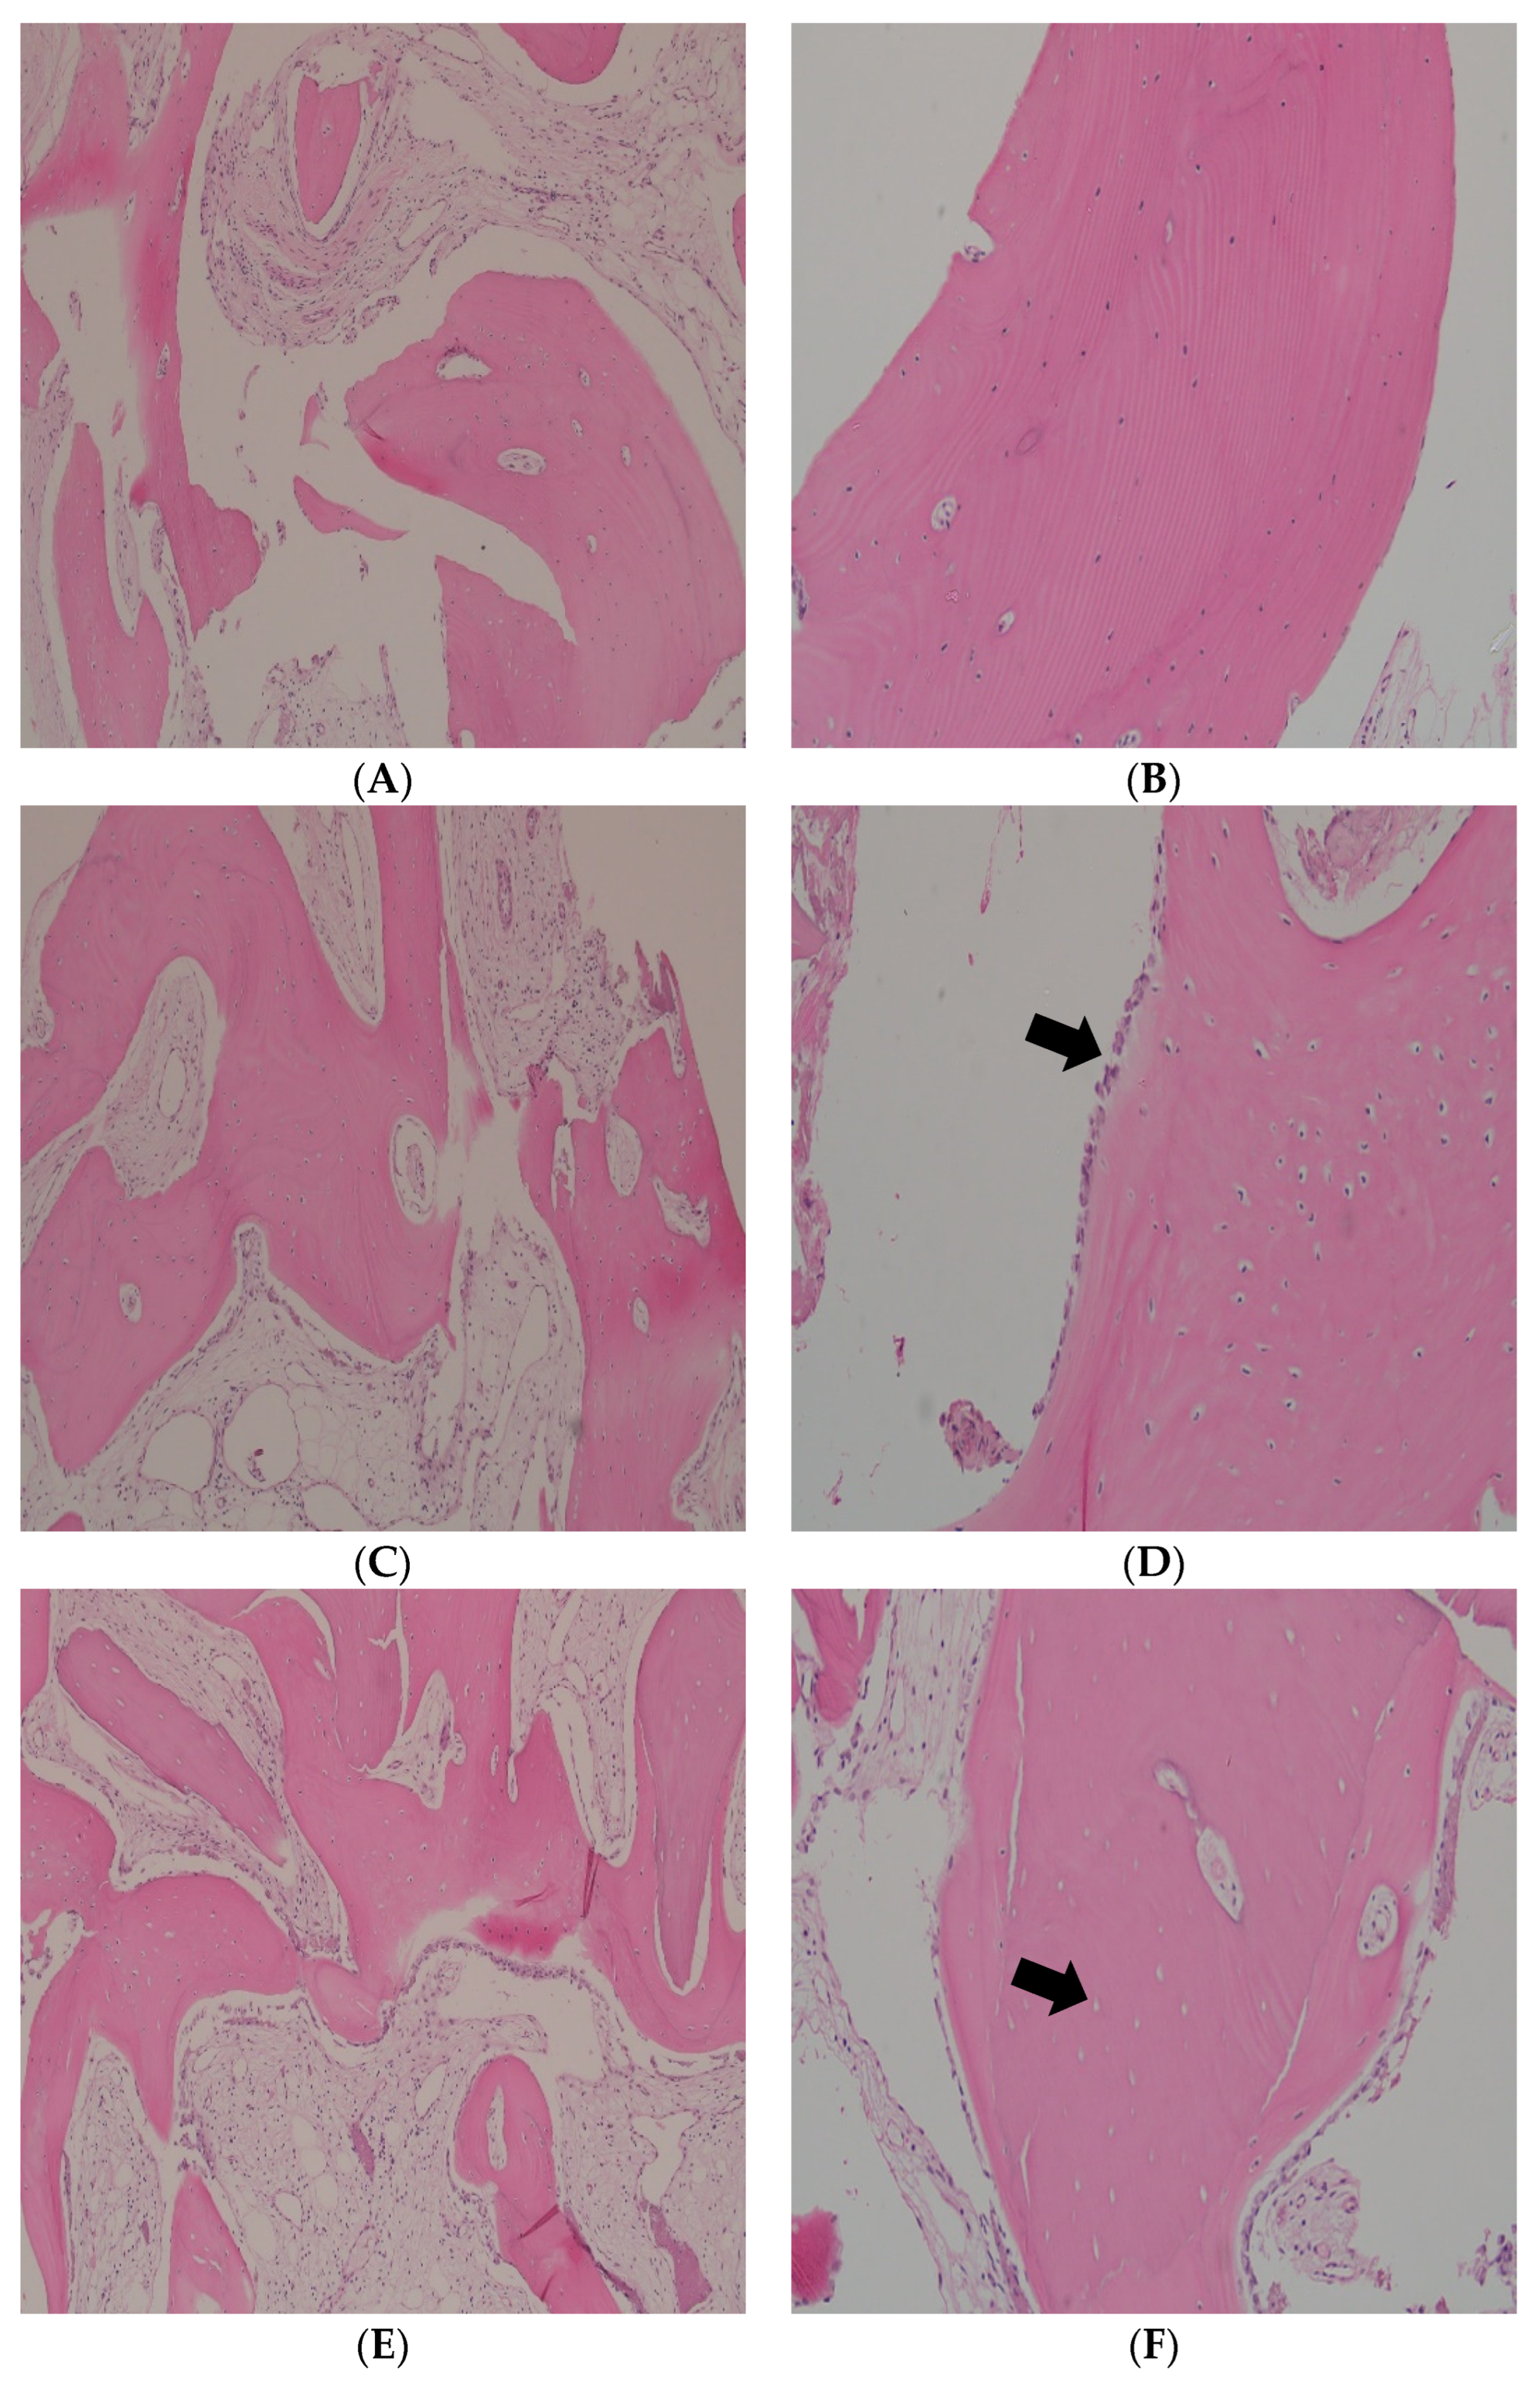

Overall, the A-PRF group showed signs of mature vital bone. However, a small fragment of immature and vital bone was focally observed in one sample. The bone marrow contained fibrofatty tissue with scattered lymphocytes and mast cells (Figure 4A,B). In the A/S-PRF group, complete mature and vital bone formation was detected, with no residual bone graft material. Few neutrophils and lymphocytes were observed within the fibrofatty marrow. In addition, some of the bony trabeculae were rimmed by a layer of osteoblasts (Figure 4C,D). In the FDBA/CM group, two specimens exhibited areas of both mature vital and immature non-vital bone embedded in a fibrofatty marrow and contained scattered inflammatory cells. Interestingly, the non-vital bone was surrounded by a rim of mature bone. These fragments of non-vital bone most likely represented graft material. The third specimen was mainly composed of mature vital bone in a non-inflamed fibrous stroma (Figure 4E,F). Finally, in the RCP group, two specimens showed mature vital bone formation with a considerable amount of fibrofatty bone marrow. In one specimen, the bony trabeculae were surrounded by fibrous tissue (Figure 4G,H).

Figure 4.

A-PRF group (A,B): Mature lamellar bone can be observed, with many osteocytes residing in the lacunae, while fibrovascular bone marrow is observed at the periphery (hematoxylin–eosin; original magnification; (A) ×10; (B) ×20). A/S PRF group (C,D): Mature lamellar bone can be observed, with many osteocytes residing in the lacunae. The fibrofatty marrow contains scattered inflammatory cells (C). Osteoblastic rimming (arrow) (D) (hematoxylin–eosin; original magnification; (C) ×10; (D) ×20). FDBA/CM group (E,F): A mixture of mature vital and non-vital bone tissue. The non-vital bone grafted bone is present in the center and surrounded by vital bone (arrow) (F) (hematoxylin–eosin; original magnification; (E) ×10; (F) ×20). RCP group (G,H). Mature/vital bone embedded in a fibrofatty marrow (G). Higher magnification to show the fatty bone marrow (H) (hematoxylin–eosin; original magnification; (G) ×10; (H) ×20).